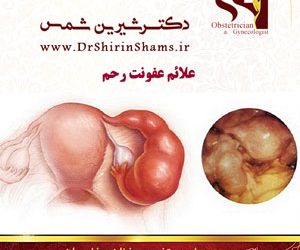

علائم عفونت رحم

به طور کلی عفونت های سیستم تناسلی در زنان شایع می باشد . عفونت هایی که در ناحیه واژینال و قسمت خارجی ناحیه تناسلی را درگیر می کند علائم عفونت رحم است . این قارچ به نام کاندیدا آلبیکنس است که با علائمی از جمله: ترشحات خشک ، سفیدی و پنیری مانند سوزش...